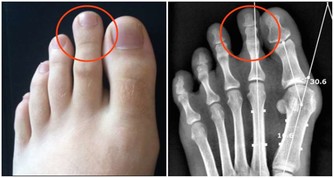

7、身邊有個大菸鬼

統計表明,美國每年有3000名非吸菸人員死於肺癌,30萬兒童患呼吸道感染,二手菸對健康的影響毋須多言。

建議:應儘量遠離二手菸環境,另外,飲酒也應適量。酒精會抑制製造抗體的B細胞,增加細菌感染的機會。